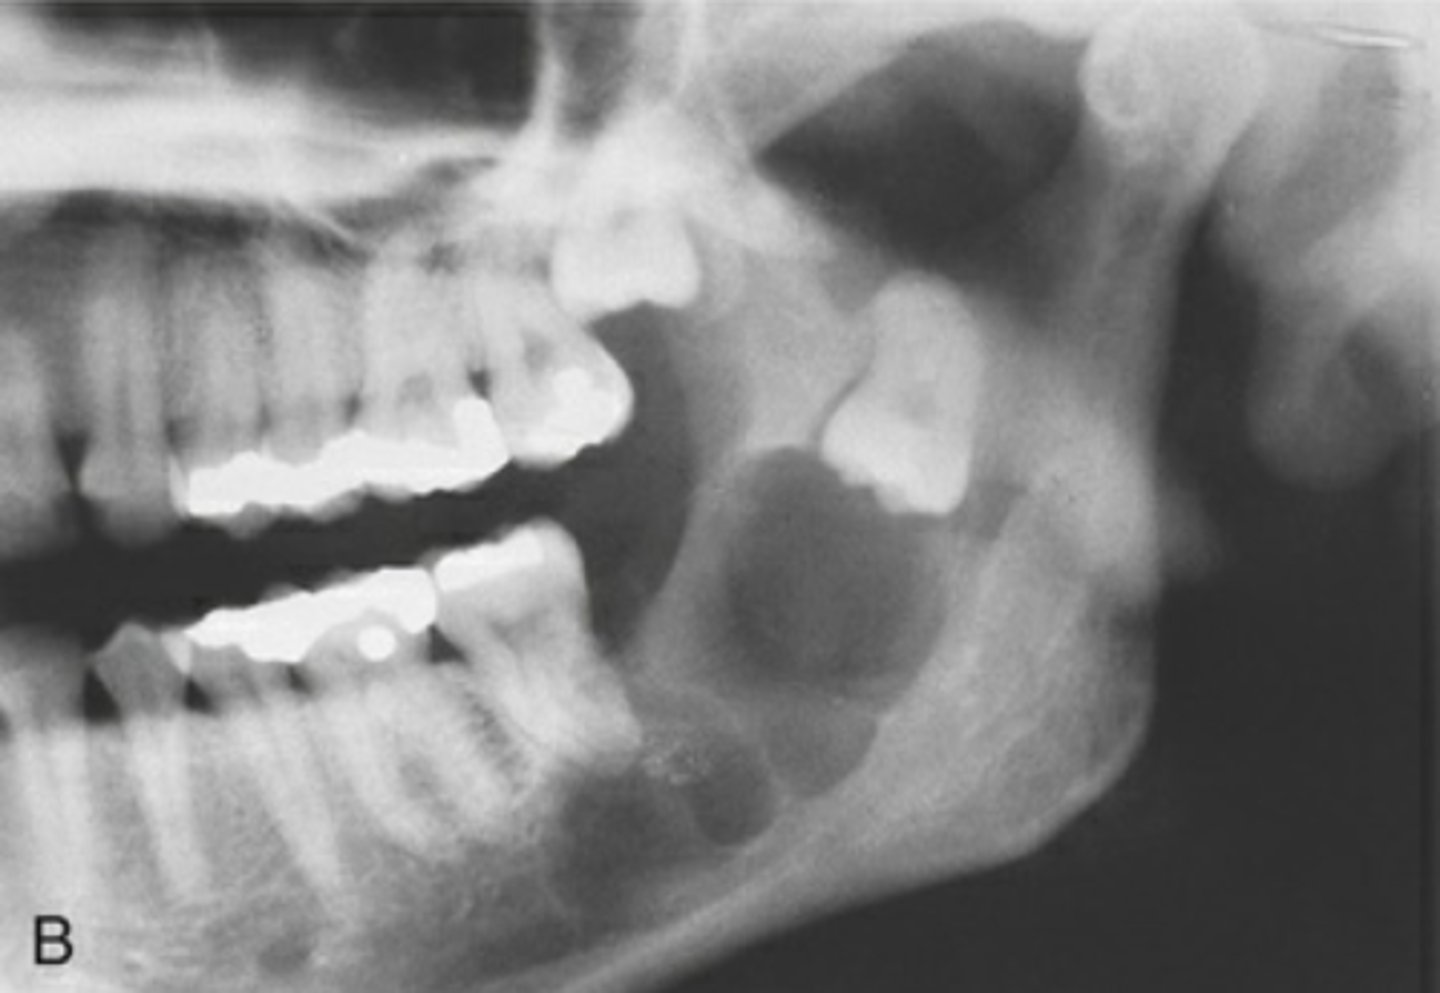

What area does odontogenic keratocyst (OKC) expand?

Mandibular posterior area

How does odontogenic keratocyst (OKC) expand around teeth?

Around entire tooth

What is the recurrence rate of odontogenic keratocyst (OKC)?

High recurrence rate

What are the differential diagnoses for odontogenic keratocyst (OKC)?

Ameloblastoma, dangerous cyst